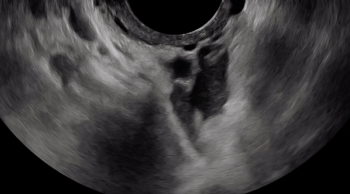

A hypoechoic deep endometriosis nodule is noted within the hyperechoic uterosacral ligament. In this case, there is an ovary containing an endometrioma fixed to the uterosacral ligament nodule.